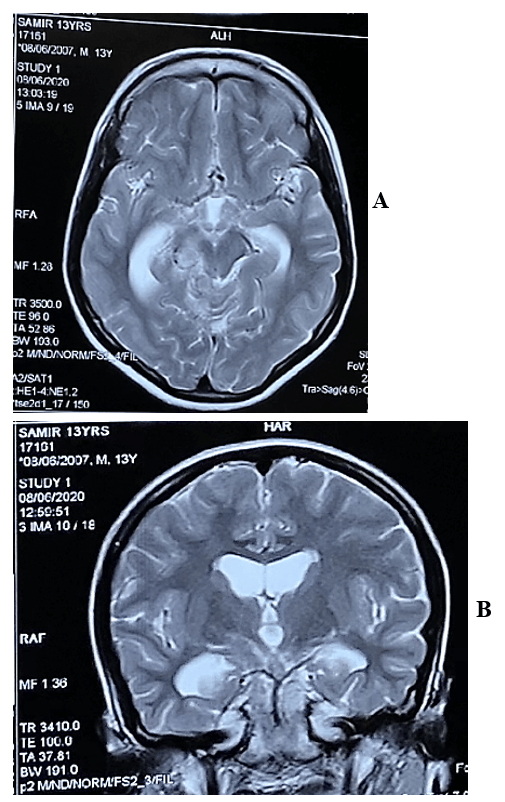

Figure 3: The lesions became heterogeneously hyperintense on T2 WI in A) axial & B) coronal view.

On the MRI T1-weighted images, multiple ill-defined mixed iso to slight hypointensity lesions were found to be located in basal, suprasellar, interpeduncular, prepontine, ambient and quadrigeminal cisterns (Figure 2) and the lesions became heterogeneously hyperintense on T2 WI (Figures 3A & 3B). The lesions were also hyperintense in FLAIR images (Figure 4) and after contract enhancement, there were multiple conglomerate ring shaped tuberculomas of 0.5 to 1cm size located at the basal, suprasellar and perimesencephalic cisterns and along the leptomeninges of basal region of cerebral hemisphere with racemose patterns. The central nonenhancing portions corresponded to caseation necrosis (Figures 5A & 5B). After treatment with antitubercular chemotherapy for 18 months the patient showed complete clinical recovery (Figure 6) but persisting radiological features of tuberculosis.